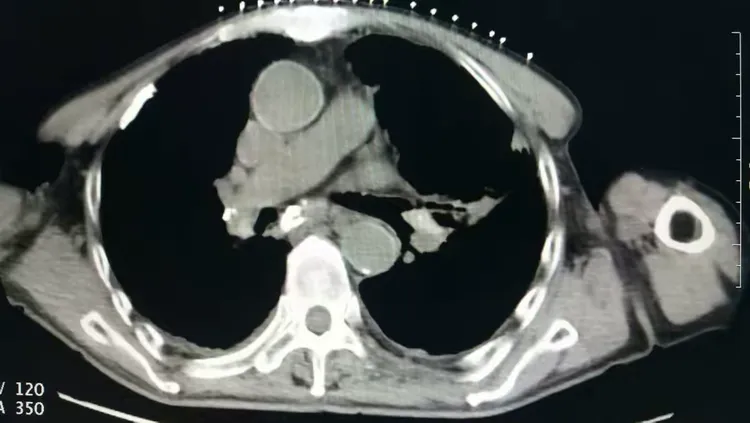

肺癌图片与正常肺图片[b0]肺部肿瘤是指发生在肺部的异常新生物分为良性肿瘤和恶性肿瘤两大类[b1]肺肿瘤和肺癌的图片肺癌长在肺叶上吗左肺囊肿是什么意思七七岁肺癌[b2]微创介入显身手不开刀消灭肺肿瘤[b3]全网资源[b4]肺肿瘤的恶性程度不能单凭大小判断[b5]肺肿瘤5cm良性几率多大当得知肺肿瘤长到5cm这样的尺寸时患者的内心[b6]老年男性右上肺结节大小16厘米手术明确浸润性腺癌老[b7]中央型肺部鳞状肿瘤能否实现治愈[b8]肺鳞癌术后复发[b9]肺上长了肿块不一定都是肺癌75岁女性2月来胸闷当地[b10]肺部病灶通过立体定向放疗之后这个肿瘤一个月之后复查已经消失了[b11]肺腺癌知多少一文带你揭秘这个肺事[b12]肺早期肿瘤究竟有多大一文读懂[b13]肺癌恶化最快的三种癌是什么肺癌是肺部的一种恶性肿瘤疾病这种疾病[b14]就是我们超过5个厘米以上的这个肺部的肿瘤我们可以先通过微创介入[b15]肺上长了肿瘤并不意味着无药可救哦首先要明确肿瘤的性质是列栽[b16]一个53岁肺腺癌晚期的病例[b17]拒绝化疗选择精准微创[b18]纵隔肿瘤严重吗是不是癌症[b19]面对体检报告上的肺结节10mm很多人心中都会升起一丝担忧这个[b20]右肺两个恶性肿瘤病人不能趴着只能躺着穿刺针刚刚好微[b21]左肺巨大肿瘤的临床决策思路分享[b22]肺部肿瘤知多少良恶性质大不同[b23]肺上有肿瘤是什么病严重吗[b24]年初手术成功实施粒子精准覆盖肿瘤区域[b25]肺鳞癌知多少一文带你全面了解[b26]肺早期肿瘤大小有讲究[b27]我院这位住院患癌的患者是得了周围型的肺部患癌而且肿瘤还侵犯[b28]6mm的肺结节在影像学上是一个相对较小的发现可能是良性的也可能[b29]患者胸背疼一个月做了ct发现肺上大肿块病理为浸润性肺腺癌[b30]5个层面讲清楚肺癌医学科普[b31]肺小结节和大肺癌有很大的区别[b32]6厘米有肺血管穿行图1并且血管有增粗[b33]肺结节是肺部影像学上的一种表现可能由炎症感染良性肿瘤等多种[b34]肺结节与肺癌的关系别再被误导了[b35]这类肺结节基本不复发[b36]得了肺癌要科学治疗这位老大伯用药两次肿瘤明显缩小家人[b37]简述常见良性肺肿瘤及其影像学特点[b38]一个不起眼的肺结节长成一个大肿瘤其实是很[b39]肺腺癌和肺鳞癌到底有哪些区别[b40]肺部鳞状细胞癌的一般存活年限是多少肺部鳞状细胞癌是一种非小细胞[b41]不开刀消灭肺肿瘤微创介入治疗快准狠[b42]患者因为胸痛就诊河津市人民医院行ct检查发现肺上长了个肿瘤[b43]瑞金胸外病例拾萃10肺类癌的诊治[b44]肿瘤2点5公分肺癌属于几期当发现肺部有一个2[b45]肺癌ct影像全解析带你读懂肿瘤信号[b46]重燃患者生命之光山东省第二人民医院肿瘤内科联合多学科精准施治肺巨[b47]12mm肺结节是肺癌几期你了解多少[b48]2cm部分实性结节恶性张力高病理浸润性肺癌磨玻璃[b49]肺结节的原因多种多样可能是由感染炎症良性肿瘤恶性肿瘤等导致[b50]202487天津医科大学总医院肺部肿瘤外科副主任医师[b51]肺结节和钙化灶是肺癌的前兆吗[b52]肺鳞癌是什么癌症[b53]2024516天津医科大学总医院肺部肿瘤外科副主任医师[b54]1肿块体积显著增大晚期肺癌的肿瘤体积[b55]肺结节癌变前可能出现的6种表现抖出健康知识宝藏[b56]肺结节早期肺癌一文解读肺部ct报告[b57]肺癌是恶性肿瘤疾病随着病情的发展可能会导致癌细胞出现远处转移[b58]1厘米的肿瘤[b59]

这个月的复查结果糟透了,肺上肿瘤疯长,已经发生了一次咳血。现在没有[s0]射波刀后肿瘤会消失吗[s1]是不是做了肺部穿刺就一定是肺肿瘤或者肺癌?[s2]图片[s3]肺上长肿瘤严重吗 小红书[s4]肺上良性肿瘤怎么办才能消除[s5]确诊为肺癌晚期。医生告知王阿姨,肿瘤发展较快,手术治疗的机会不大。[s6]后,医生的诊断结果让所有人震惊——是肺部恶性肿瘤,且已经是晚期了。[s7]右肺尖肿瘤,16个月迅速长大[s8]吸烟30年,虽已戒烟5年,但这个患者的肺黑得吓人,肺上的恶性肿瘤更加触目惊心![s9]岳母肺部肿瘤病情演变[s10]肺部肿瘤[s11]新方法可能减少肺部肿瘤的生长[s12]微信图片_20190404112215.jpg[s13]胸部肿瘤综合治疗之一肺癌篇~~~科大二附院胸外科胡举副主任医师治疗体会[s14]考虑肺部肿瘤[s15]肺部的恶性肿瘤[s16]肺部肿瘤[s17]右肺上叶肿瘤,穿刺难度大,患者高龄基础疾病多,手术中并发症风险大。[s18]麻烦给看一下我的肺部有肿瘤吗?谢谢了?[s19]肺上肿瘤切除手术好做吗(肺部肿瘤位置尴尬)(1)[s20]肺部巨大肿瘤[s21]少见!6厘米巨大肺部肿瘤—兖矿新里程总医微创切除![s22]查发现患者肺部也有一个肿瘤,考虑患者原发肿瘤在肺部,脑部是转移瘤。[s23]右肺上叶贴水平裂的肿瘤,手术切除范围的考量(病例回顾)[s24]肺部长肿瘤的症状[s25]这是一名35岁女性,左肺上叶将近4厘米的肿物,没有任何症状,查体时才发现,4厘米的肿瘤都没有临床症状,还是很可怕的。腔镜下切除,淋巴结应该不至于有转移,还是略偏早期,但术后是需要靶向药物治疗或者化疗的,尽量降低复发概率。所以,肿瘤不能等有了症状再就诊,分期晚了医生也没有办法。[s26]以前照片[s27]患者高龄基础疾病多,手术中并发症风险大。术前ct见右上肺肿瘤术中操作[s28]肺肿瘤影像大汇总,看完深刻理解[s29]发展,甚至肺上的肿瘤已经缩小了百分之四十,于是在2019年1月3日出院了。在进行了四个疗程的治疗后,[s30]肺上长肿瘤严重吗 mip.haodf.com[s31]肺上长肿瘤严重吗 来自网易[s32]右肺尖肿瘤,16个月迅速长大[s33]肺肿瘤有哪些危害[s34]肺肿瘤[s35]肿瘤标记物虽然是正常的,但是咳嗽原因不明,ct却发现肺上长了肿物.[s36]肺部恶性肿瘤需要手术吗能治好吗[s37]肺上长了肿瘤必须要做穿刺检查吗?[s38]肺部肿瘤能治好吗[s39]